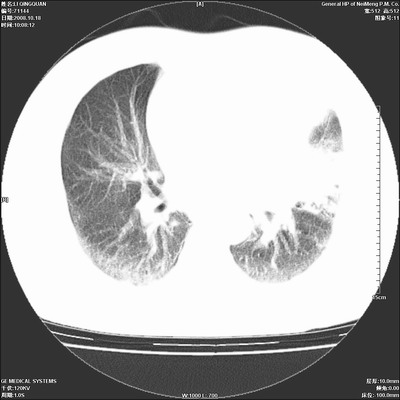

以下是引用duguo在2008-10-19 13:59:00的发言:[br]左肺上叶支气管狭窄,首先考虑中心型肺癌伴阻塞性肺炎\\肺不张.

以下是引用ybing在2008-10-19 12:58:00的发言:[br]左肺上叶阻塞性炎症-建议支气管镜进一步检查除外中央型肺癌

以下是引用随光逐影在2008-10-19 14:31:00的发言:[br]考虑左肺中央型肺癌并左肺上叶阻塞性肺炎,肺不张。